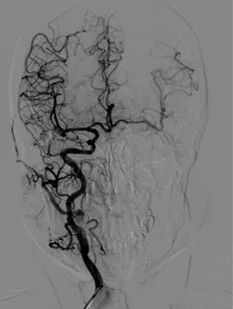

入院影像检查

导丝怎么扩重磅!NOVA颅内药物球扩支架湖北首例植入!_https://www.jmylbn.com_新闻资讯_第4张

DWI

MRI(T2Flair)

导丝怎么扩重磅!NOVA颅内药物球扩支架湖北首例植入!_https://www.jmylbn.com_新闻资讯_第5张

MRA

重要影像结论:左侧大脑半球内侧多发陈旧性梗死灶,左侧颈内动脉C4段重度狭窄。